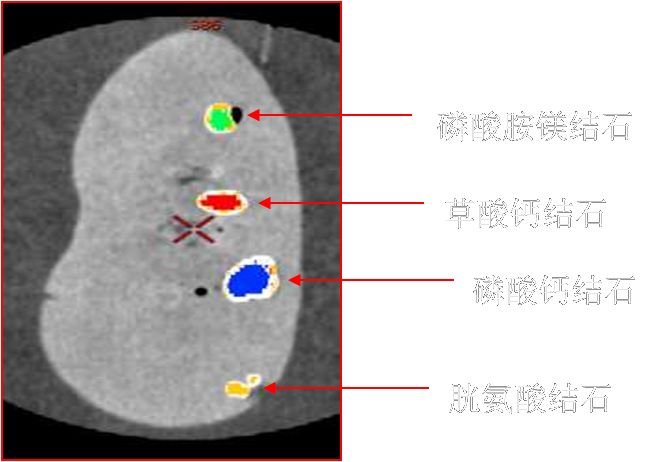

泌尿系统常规化精准能谱成像:

结石成分分析、痛风分析等。